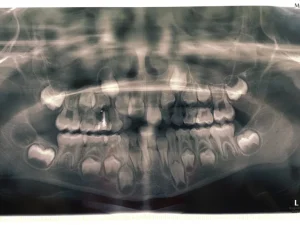

Last week Amy and I visited St Joseph’s Catholic Primary School in Newbury to talk to the year 4 students about their oral health. I started by talking about the different teeth that we have, their shapes and what they are used for and we looked at how different animals have different shaped teeth according to their diet. We also talked about how to look after their mouths and what can happen if they don’t look after their teeth. The children were very enthusiastic and interactive with lots of patient hands in the air waiting to tell us their stories and ask questions. We got a little side tracked and with the help of Amy looked at an X-ray to show the baby teeth and also the permanent teeth waiting in the jaw to erupt. I was really pleased with the response and general enthusiasm from the children, they had already done some experiments looking at the effects different drinks had on egg shells and were keen to learn more.